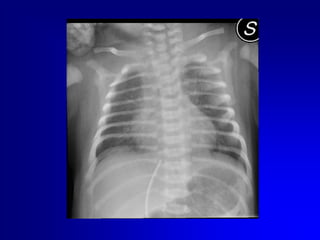

Eseguire sempre controllo radiografico o ecografico della posizione del catetere..

Eseguire semprecontrollo radiografico o ecografico della posizione del catetere..